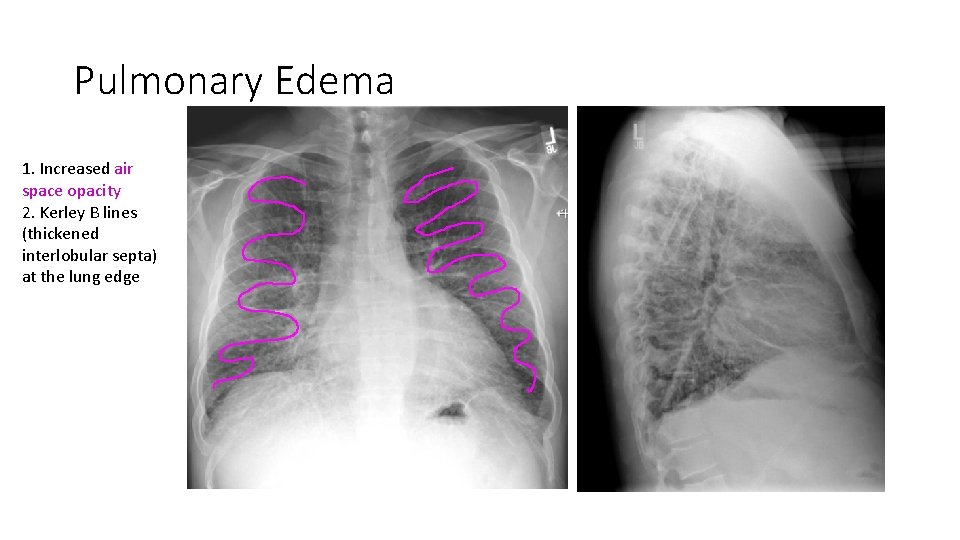

Pulmonary Edema 1. Increased air space opacity 2. Kerley B lines (thickened interlobular septa) at the lung edge